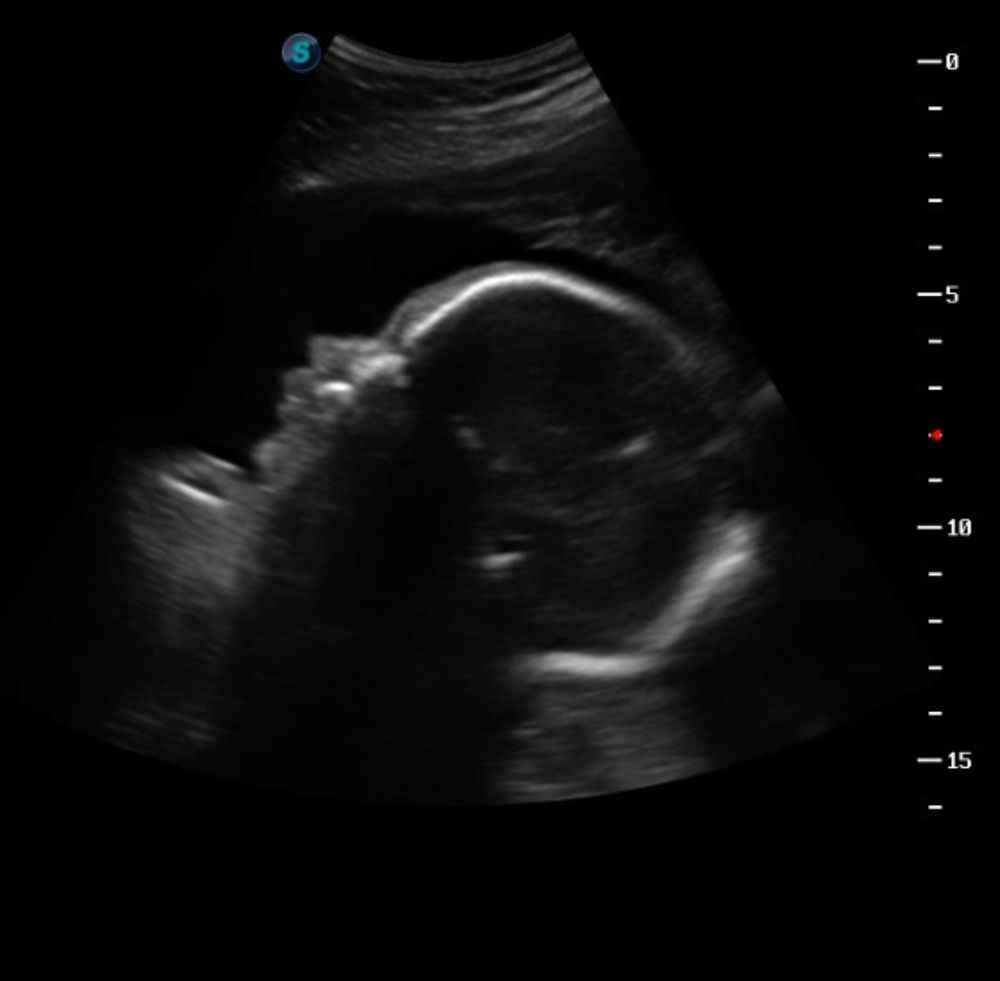

28 недель беременности 🥰

Мои неделькиСходили на встречу с нашим солнышком 💙 Перед УЗИ порадовала его гранатовым соком, чтобы он не сидел в одном положении и наконец-то показал нам носик. А то в прошлый раз как лежал анфас, так и не сдвинулся с места 😂

Сразу же с первых секунд на экране показалось личико. Роман Антонович уже такой щекастенький и губатенький, я не могу 🥹 Лежал причмокивал губами, трогал указательным пальчиком носик, разминал перед собой кулачки. Пинал датчик, из-за чего долго не получалось померять некоторые параметры 😁 Но всё равно хочется его похвалить. Сегодня помогал нам, позировал на славу. Наш любимый мальчик 💙

Как я шутила сегодня с подругами: «Я настолько люблю носатых мужчин, что рожу такого же» 🤣 Не могу налюбоваться на профиль: такой точёный 😍 Мне кажется, на мужа будет похож. Счастье 💋

По всем параметрам малыш соответствует сроку. Кровотоки отличные, шейка тоже порадовала. Всё хорошо 💙🙏🏻 Записалась на третий скрининг на 15 мая. А там туда-сюда - и возьмём нашу крошку на руки. Поскорее бы наступил этот момент 😍 Родов боюсь до одури, но желание увидеть малыша сильнее.